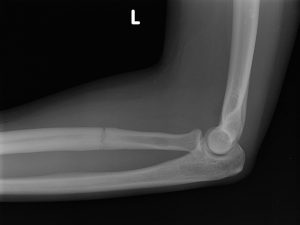

Las fracturas por estrés pueden ocurrir en huesos sometidos a presión constante y repetida, por sobreuso, o micro traumatismos repetidos. Pueden ocurrir en los pies, la rodilla, tibia, peroné, cuello femoral, vértebras, antebrazos etc.

Se puede sospechar el diagnóstico al examinar al paciente y escuchar su historia clínica, Las Rx en algunas ocasiones pueden mostrar la lesión, pero generalmente pasan desapercibidas en los primeros días de los síntomas. La RESONANCIA MAGNÉTICA es el exámen más preciso que puede revelar la lesión y confirmar el diagnóstico que se sospecha.